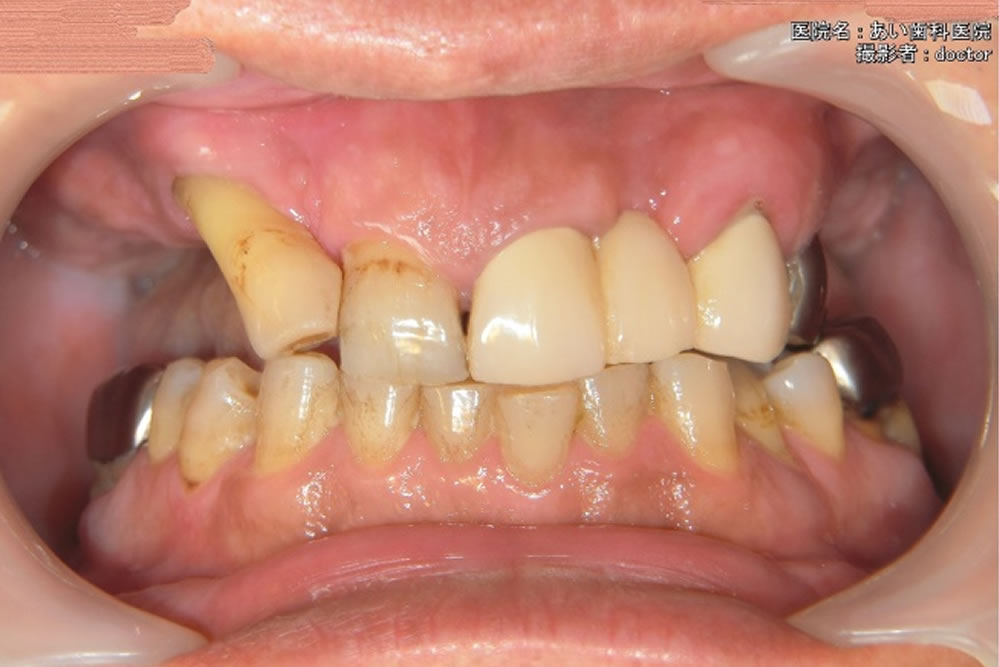

コンフォートデンチャースポーツで咬み合わせを回復した症例

コンフォートデンチャースポーツで咬み合わせを回復した症例(60代 男性)

1年ほど前に保険の部分入れ歯の治療を他院でされたのですが、違和感が大きく、しゃべりにくい、あたって痛いと困っておられました。結局、入れ歯はすぐに使わなくなり、それから歯がない状態が続いたそうです。以前の歯医者さんでは、慣れれば使えるようになると言われたそうですが、全く使う気になれような状況ではなかったとのことです。

最初の相談、治療計画の段階ではインプラント治療、数種類の入れ歯など様々な治療方法を検討しました。欠損歯(自分の歯がない部分)の数が多いため、入れ歯を第一選択とし、その中でも、しっかり強く噛める入れ歯にしたいとの希望で、コンフォートデンチャーの「スポーツ」を選ばれました。

スポーツを選んだのは、金属にチタンを使用しており、薄く、軽いところです。スポーツジムに通っているご本人からも是非との希望でした。咬合に大きな負荷がかかることも想定し、スポーツは通常よりもシリコンが厚めになっています。